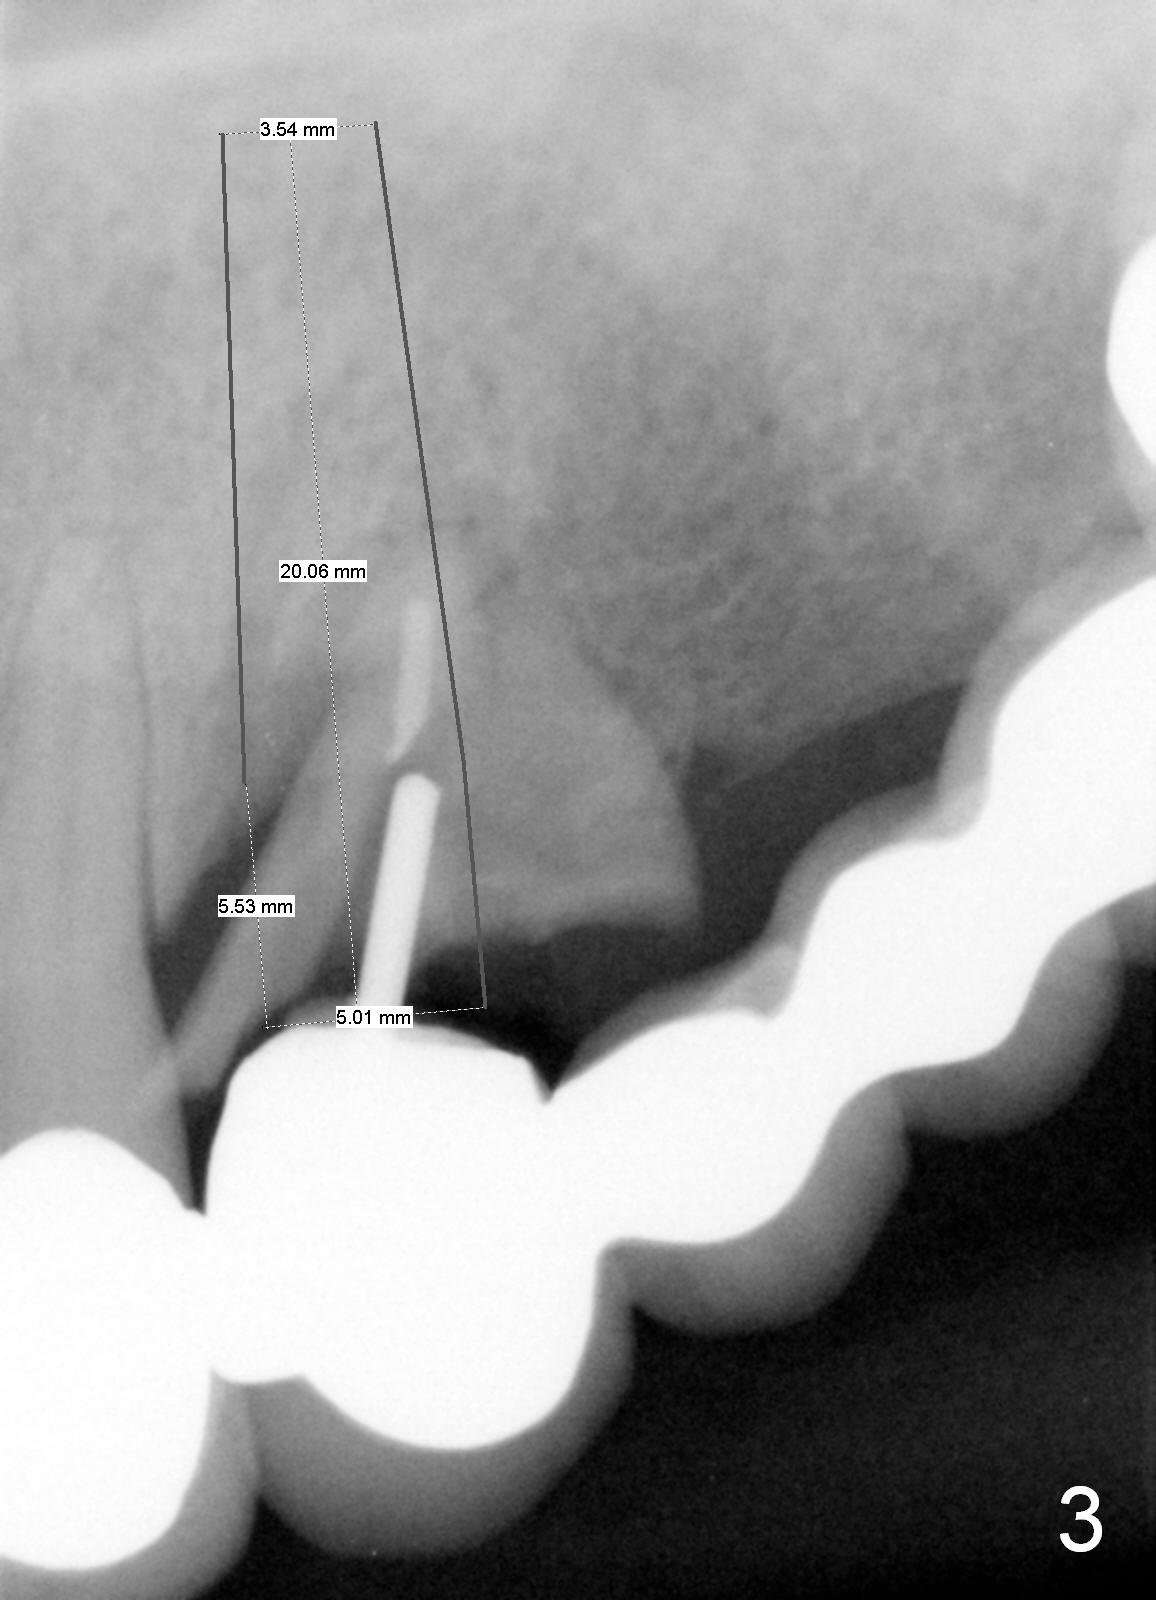

A 68-year-old female has had a long spanned FPD (fixed partial denture, bridge) for the last 2 years.  It is loose (Fig.1,2).  The patient is concerned about cosmetics, but has limited finance.  The FPD dislodges when Alginate impression is being taken.  The teeth #11 and 15 will be extracted and replaced immediately by implants (Fig.3,4).  After placement of abutments, a 5-unit immediate provisional FPD will be fabricated if the implants achieve primary stability.  Otherwise, an additional implant will be placed at the site of #13.  There will be no occlusal contact.